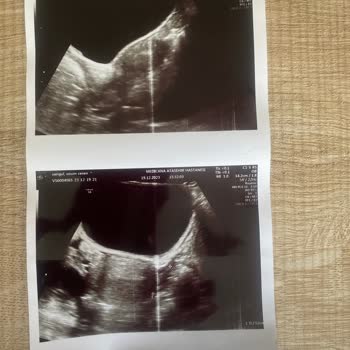

Tüp bebek sürecine başlamadan önce test sonucunun yanlış olma ihtimalini ve tekrar yapılması gerekip gerekmediğini sordum. 'Sonuç değişmez, tekrar yaptırmanıza gerek yok.' diyerek bizi sürece başlamaya ikna etti. Sürece hsg (rahim filmi) çektirerek başladık ve rahmimin y şeklinde olduğu, hamile kalmak ve hamileliği sürdürebilmek için histeroskopi operasyonu gerektiği söylendi.

Amh değerinin yükselmeyeceğini biliyoruz, bu da demektir ki hastanenizde yanlış ölçüm yapılmış. Daha sonra tekrar hsg çektirerek rahmimdeki y şeklinin değişmediğini ve hastanenizde geçirdiğim histeroskopi operasyonunun başarısız olduğunu öğrendim.

Görüştüğüm doktorlar histeroskopinin hem başarısız hem de gereksiz olduğunu ifade ettiler. Tüm bu gereksiz ve başarısız işlemlerden sonra 11 haftalık hamileyim ve son derece sağlıklı bir gebelik geçiriyorum.